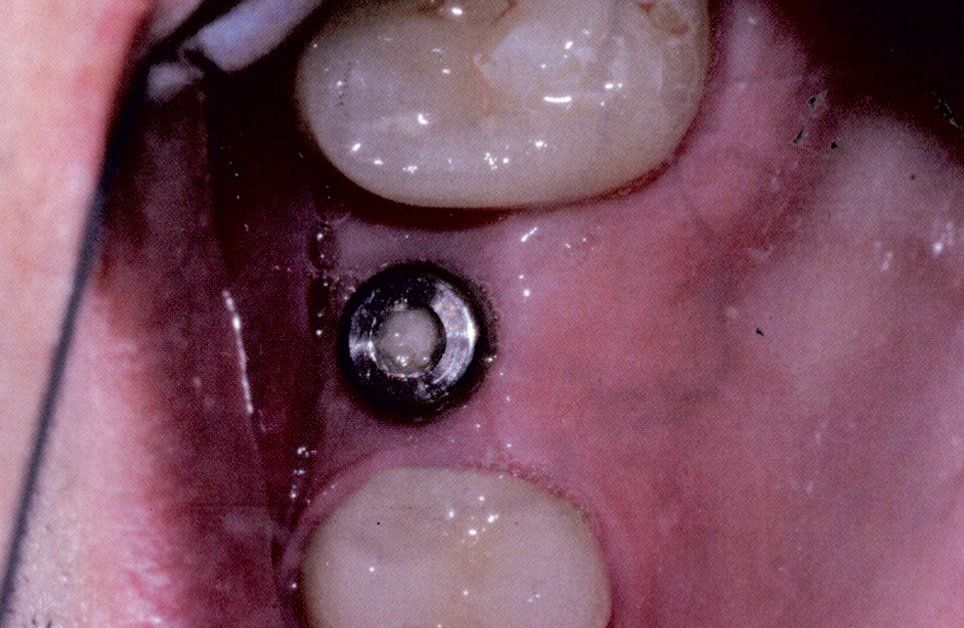

Sostituire denti mancanti è possibile grazie alle tecniche acquisite nel campo dell'implantologia, la branca del settore odontoiatrico che si occupa di inserire protesi fisse o impianti dentari.

In questo caso si tratta di implantologia a carico immediato.